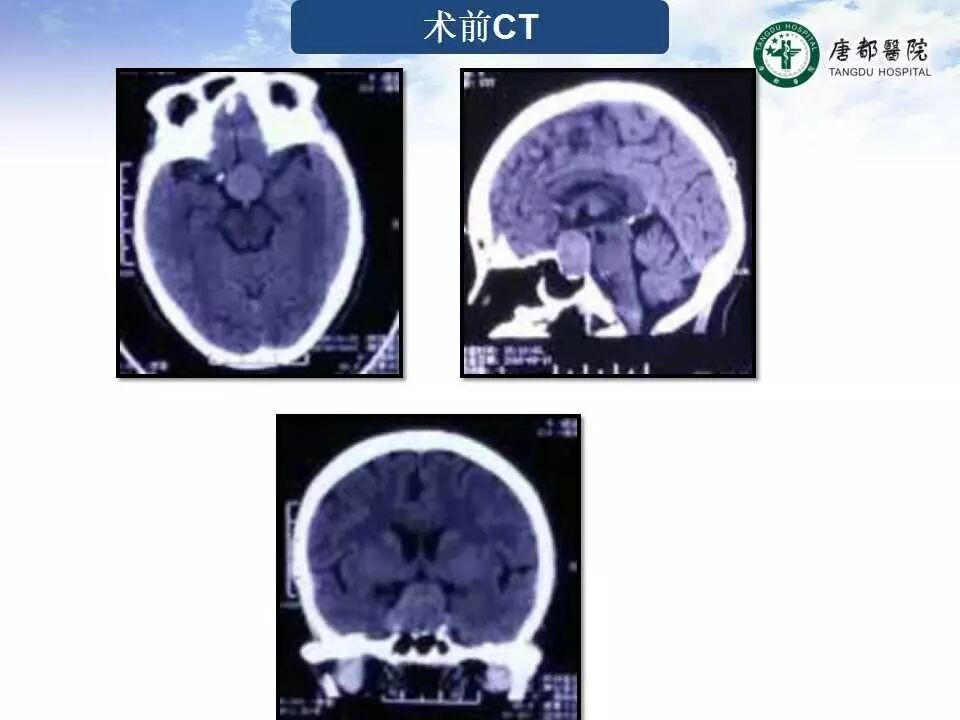

Case 4

长按并识别二维码即可查看该手术视频